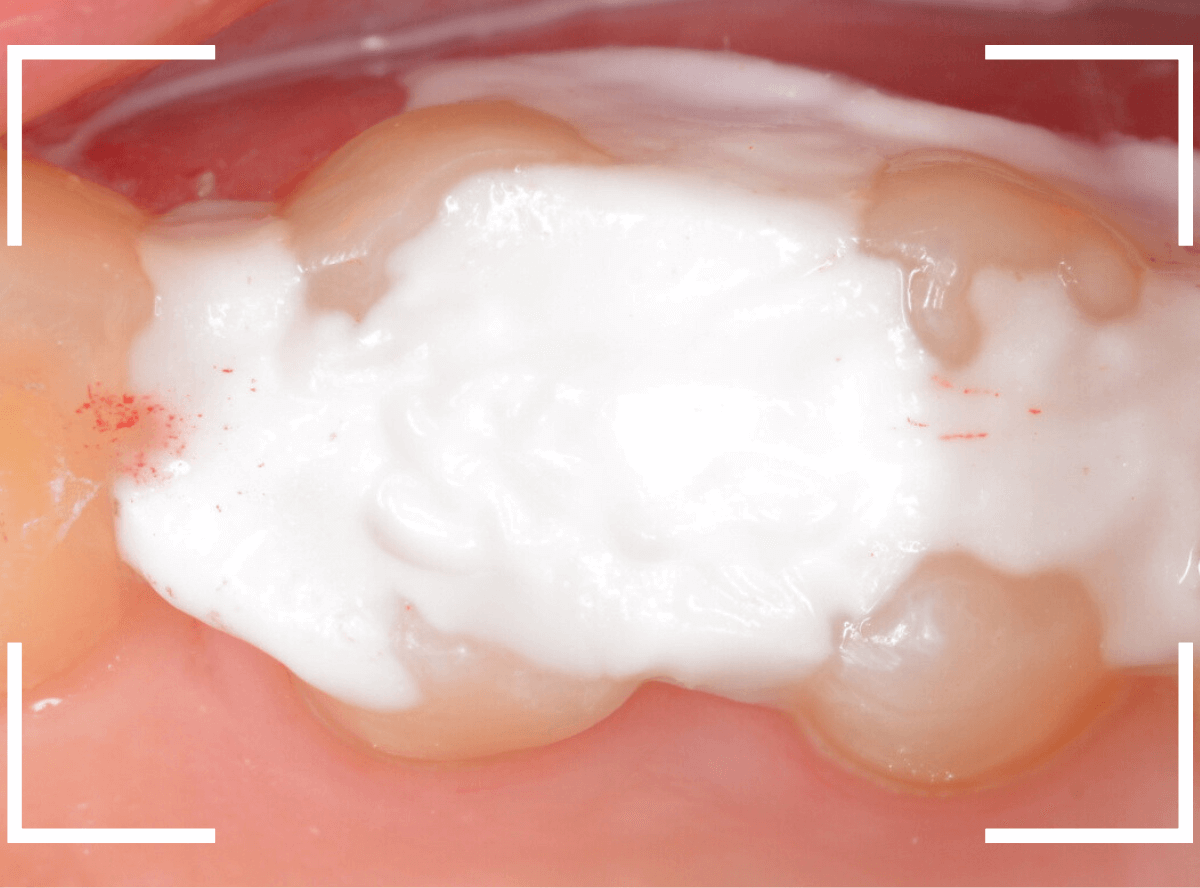

慎重に全ての虫歯を除去しました。

何とか、神経が露出せずに済んでいます。

お薬をつめて、セメントで蓋をして経過観察します。

後日、状況を確認したところ、虫歯処置した後も、手前の奥歯が痛むとの事でした。

「我慢できないほどでもない」との事でしたので、引き続き経過観察しつつ、奥歯の治療を治療する事になりました。

奥歯もお薬をつめて、セメントで蓋をして経過観察です。

何とか神経を取らずに済ませたいですが、どうなる事か・・・。